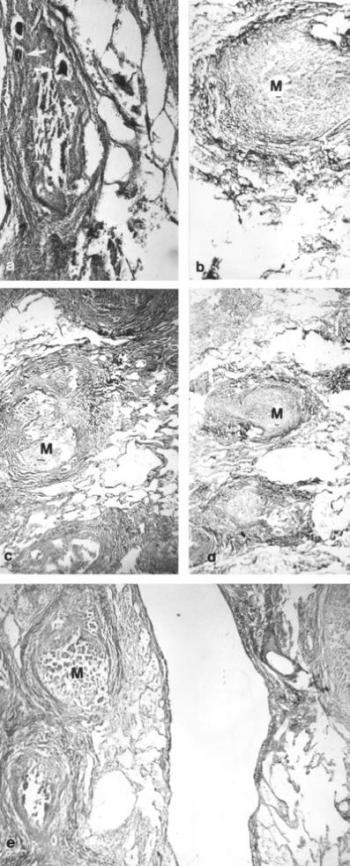

113. ábra. a) Miliaris tuberculum (M), szélén Langhans típusú óriássejtek körvonalaival (nyíl). Gömöri ezüstözés, 240× nagyítás b) A miliaris gümő körül csekély rostképződés mutatható ki. Gömöri ezüstözés, 240× nagyítás c)-d) Valamennyi tüdőlebenyben elsajtosodott miliaris gócok. Pikrosziriusz festés 100× nagyítás e) A gümők környezetében vikariáló emphysema. HE festés, 100× nagyítás 1801-ben elhunyt 19 éves nő